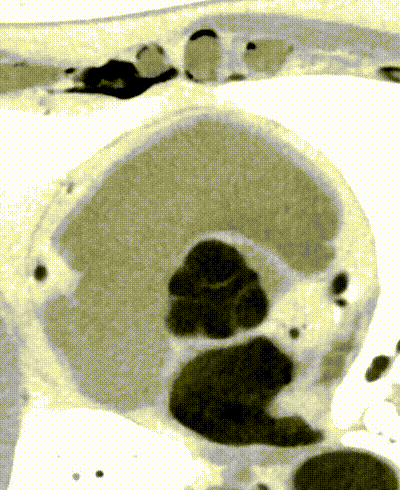

以心脏瓣膜疾病为例,CT影像已逐渐成为拟定TAVR手术策略参考的金标准。针对主动脉瓣周围的结构数据测量及瓣膜运动评估,临床中需要依赖全时相CTA扫描获取主动脉根部图像。然而,受限于患者心率、屏气效果以及设备扫描能力等因素限制,部分时相下图像运动伪影严重,无法获得高质量的全时相CTA图像。仅通过特定时相静态高清成像,难以准确清晰呈现瓣膜等结构在整个心动周期内的动态变化。

全心4D电影成像

展示心脏结构运动

传统CT通常只能提供单时相静态结构成像,但uCT SiriuX打破了局限,可提供全心动周期多个时相的清晰结构成像信息,动态展示心脏结构运动变化,达到了类DSA、类MR的效果。

瓣膜运动

心肌运动

单心动周期全心4D电影成像

如此一来,便可进一步帮助精准测量冠脉狭窄程度、观察狭窄变化及斑块应力变化,进而预测斑块进展与破裂。此外,图像清晰展示瓣膜开合运动,为瓣膜的结构完整性评估和尺寸测量提供可靠依据,具有重要的潜在临床应用价值。